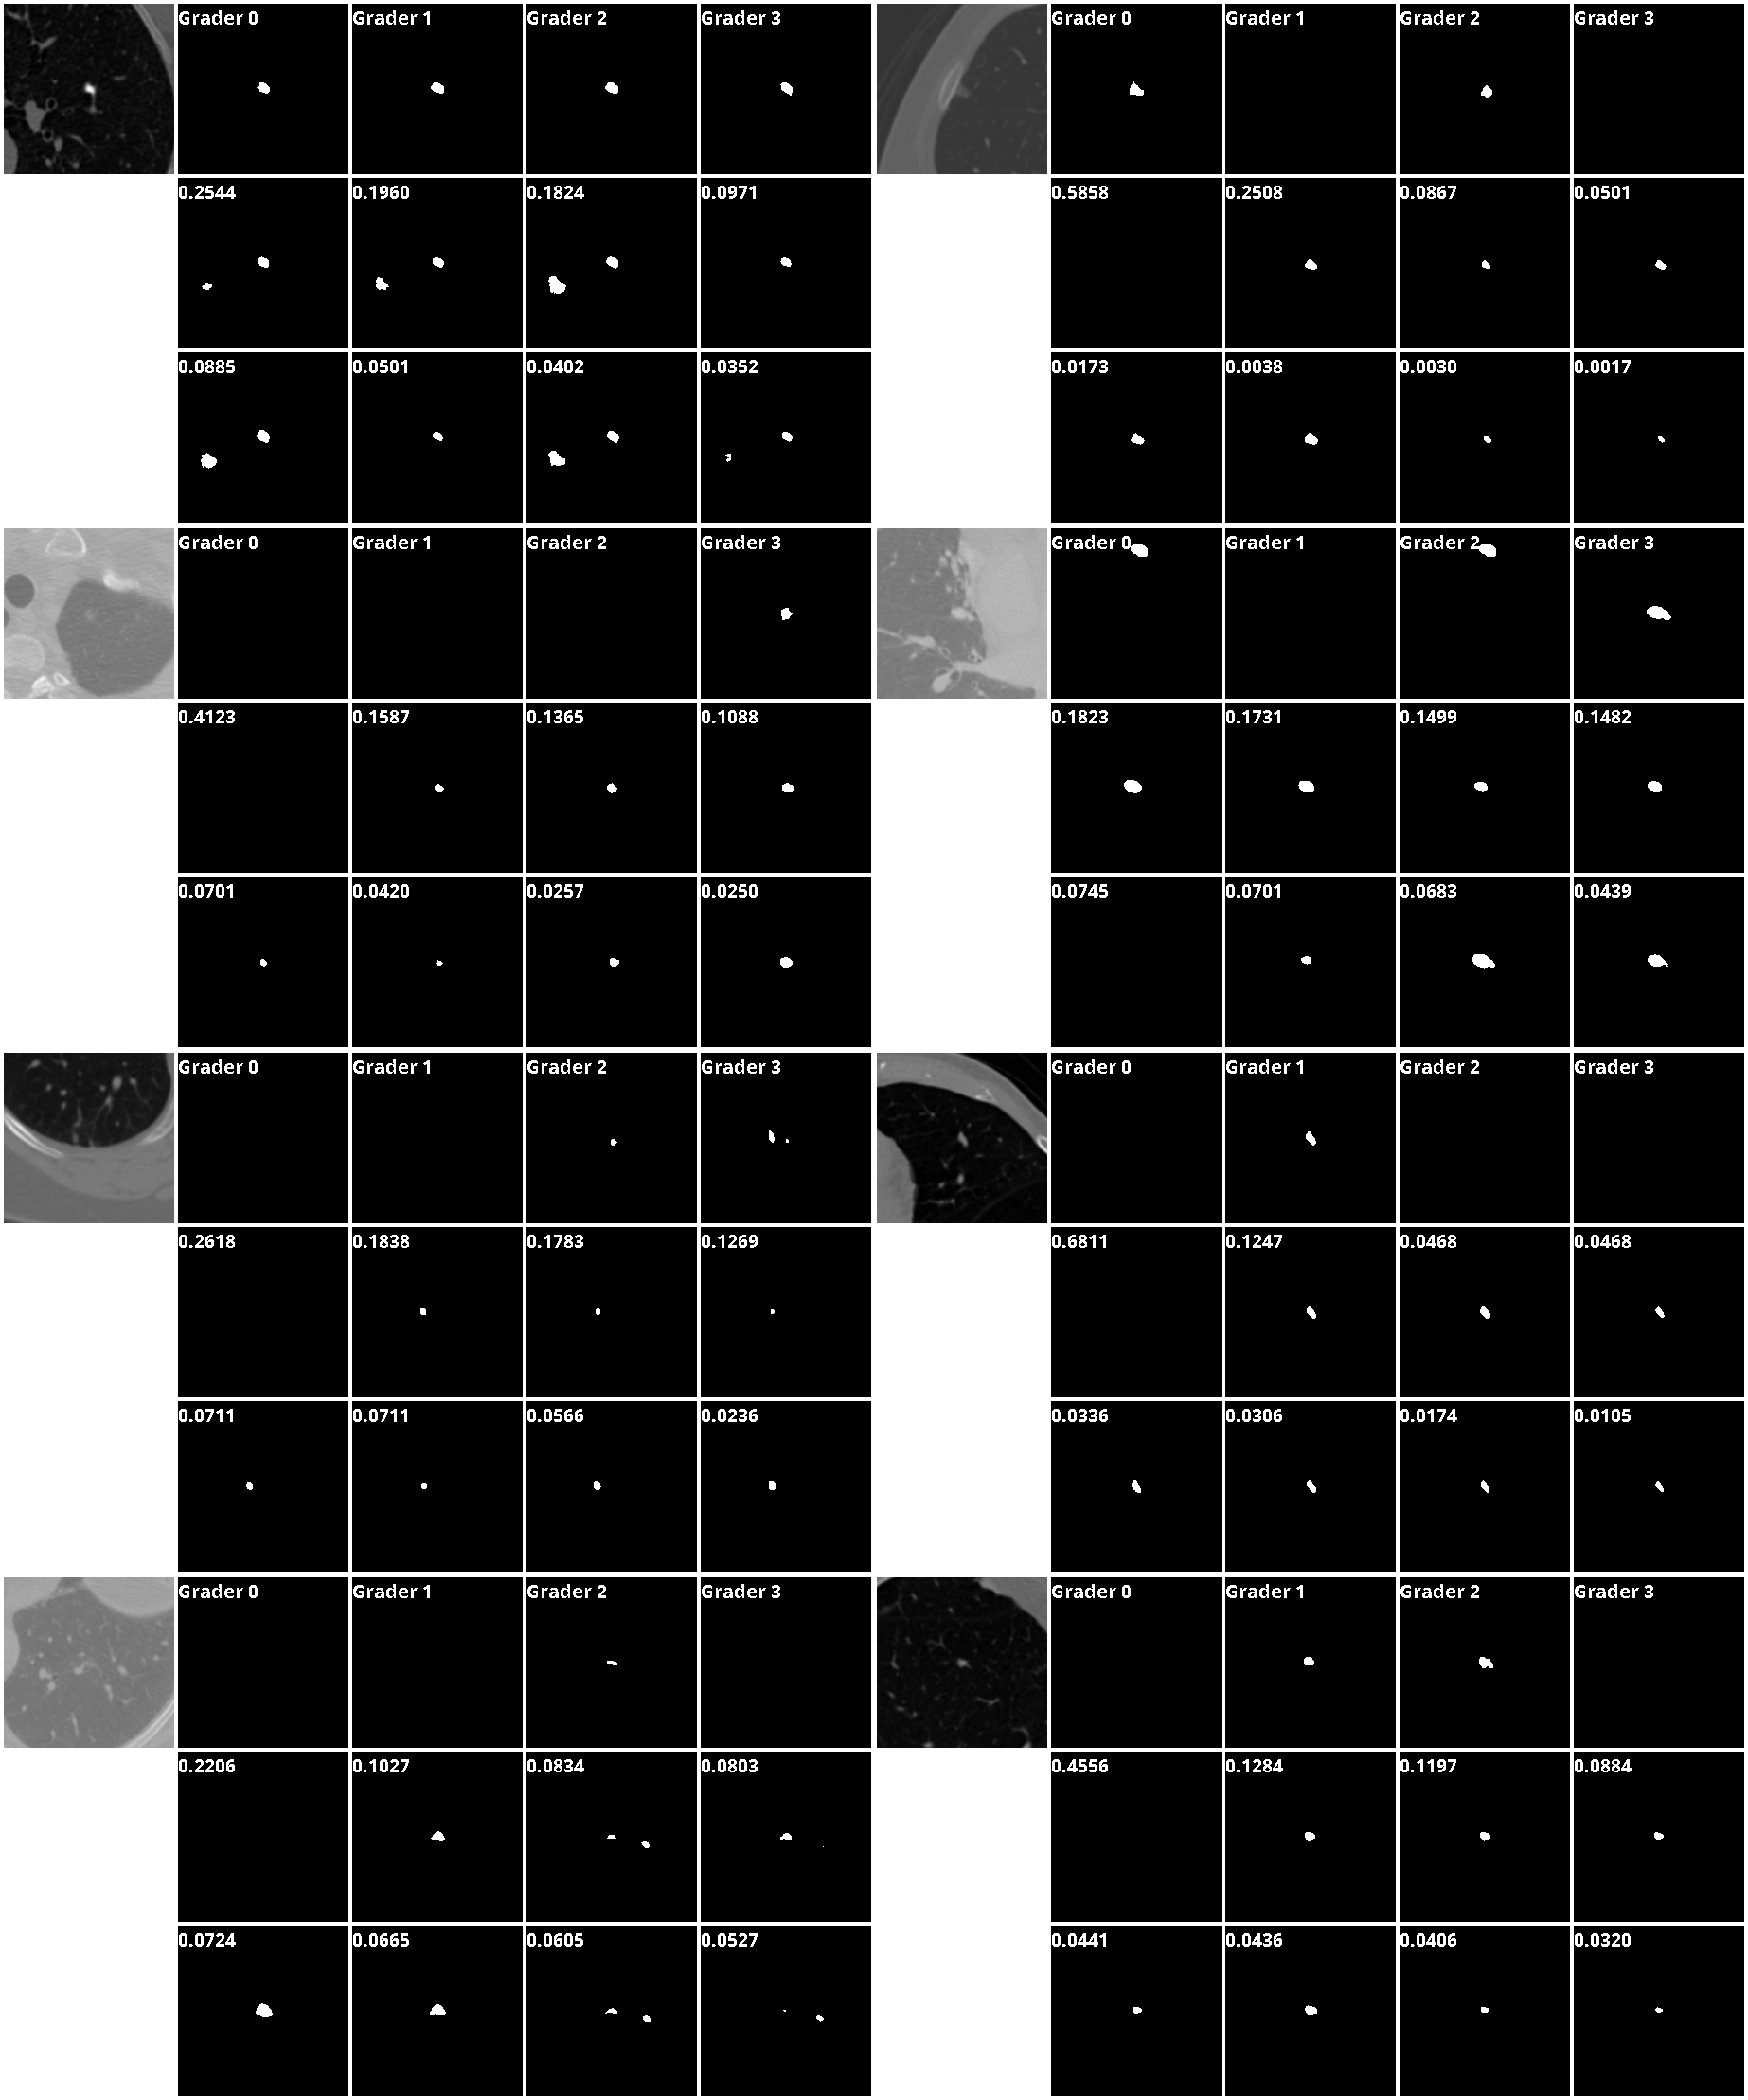

Figure 4: Visualization of our results on the highly ambiguous samples from LIDC-IDRI dataset. The first row shows the input samples and their segmentations, and the next two rows show the top-8 predictions from our method. The uncertainty estimation for each segmentation proposal is annotated on the upper-left corner.

We use the LIDC-IDRI dataset provided by Armatoย III etย al. (2015; 2011); Clark etย al. (2013), which contains 1018 lung CT scans from 1010 patients. Each scan has lesion segmentations by four (out of totally twelve) expert graders. The identities of the graders for each scan are unknown from the dataset. Samples from the testing set can be found in the first row of Fig.4. As can be seen, the graders are often in disagreement about whether the scan contains lesion tissue. We hypothesize that the disagreement is due to the different assumptions the experts have about the scan. For example, judging from the scanโ€™s appearance, one of the graders might have believed that the suspicious tissue is in fact a normal tissue based on his/her experience, and thus gave null segmentation. There are also other possible underlying assumptions for the graders to come up with different segmentation shapes.

Our task is to identify such ambiguous scenarios by proposing distinct segmentation results from the corresponding latent hypotheses with their associated probabilities, which will be helpful for clinicians to easily identify possible mis-identifications and ask for further examinations of the patients.

Some sample testing results predicted by our model to have high uncertainty are illustrated in Fig.4. The first row is the input and its four segmentations, and the last two rows are our top-8 predictions, where the probability associated to each latent code is annotated on the upper-left corner. We can see that our method can capture the uncertainty that is contained in the segmentation labels with notable probability scores, as well as other type of segmentations that seem plausible without further information.